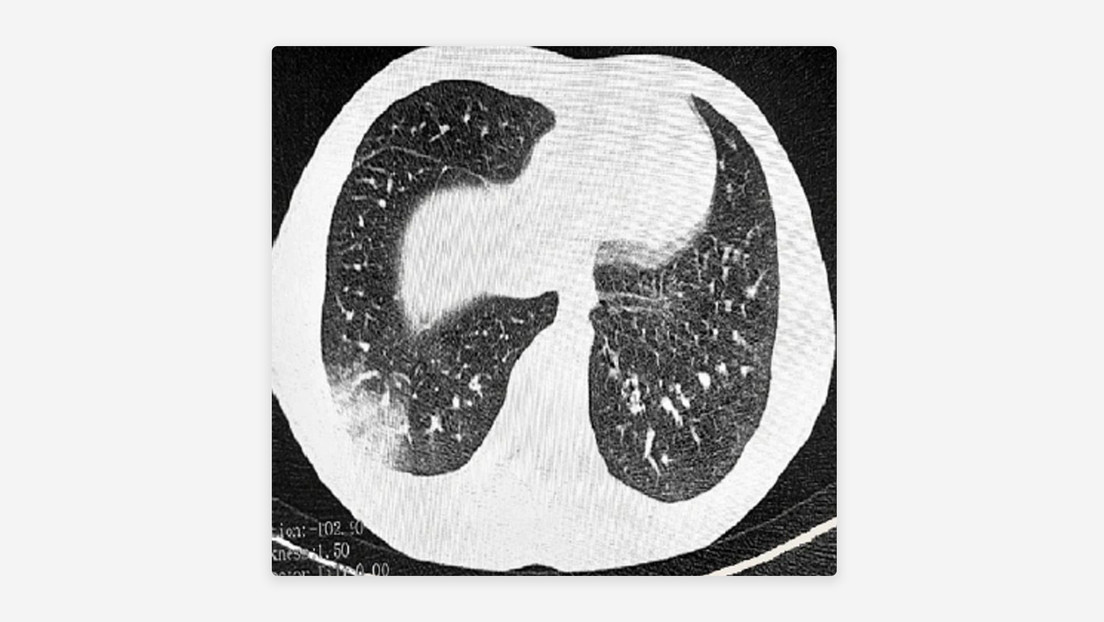

Durante el periodo de seguimiento, los investigadores encontraron más de 23.000 casos de hipertensión, más de 13.000 nuevos casos de diabetes tipo 2 y cerca de 8.000 casos de EPOC. Al final, los usuarios de cigarrillos electrónicos eran más propensos a desarrollar EPOC. Un subgrupo específico de entre 30 y 70 años presentaba un mayor riesgo de hipertensión.

La EPOC se produce cuando los pulmones no dan abasto y la persona que la padece le cuesta respirar durante largos periodos de tiempo.